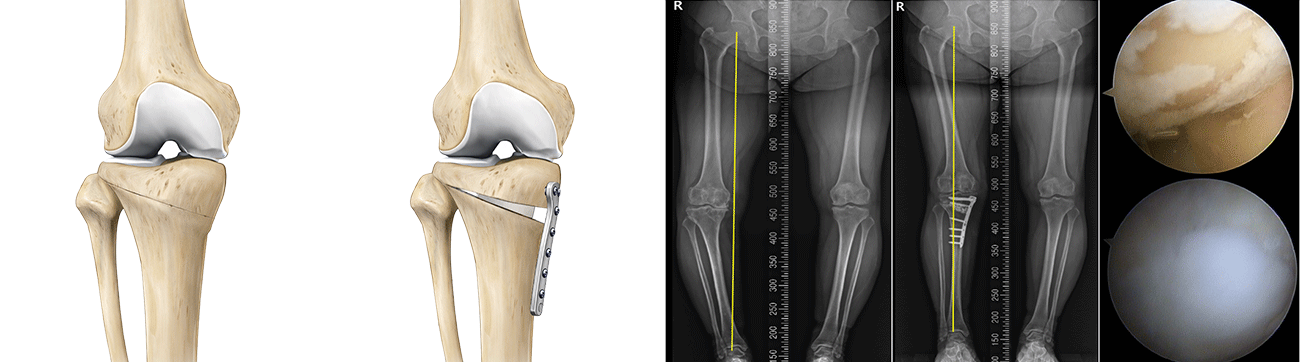

근위경골절골술은 오다리 변형으로 인해 무릎 안쪽 관절에 집중되는 체중 부하를 교정하기 위한 수술입니다.

무릎 아래 뼈인 경골의 정렬축을 조정하여, 이를 통해 무릎 안쪽 연골에 집중되던 부담을 줄이고 통증 완화를 기대할 수 있습니다.

마치 오래된 자동차 타이어에 편마모가 생기면 위치를 교환하여 사용 수명을 늘리는 것과 같은 원리입니다.

여기에 연골의 근본적인 재생을 유도하는 줄기세포(카티스템) 연골재생술을 결합한다면 무릎 관절의 수명을 늘리는데 더욱 도움이 됩니다. 결과가 좋은

환자분의 경우에는 평생 무릎 인공관절을 안하는 경우도 있을 정도로 예후가 우수한 치료법입니다.